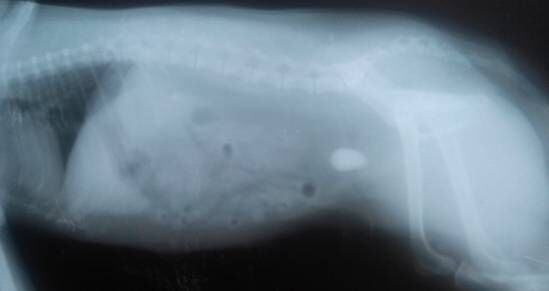

X光下,另一个病例中膀胱内结石。

根据结石发生的部位不同,采取的手术方案也不尽相同。可以很快解除临床上出现的症状,手术治疗因为不能从根本上解决结石发生的原因,不能降低结石复发的概率。图中所示的两张X光片中,为两个单独的病例,结石的位置都位于膀胱内。同时也需要无菌逆向从尿道口插入导尿管来确定尿道是否有结石,正向、逆向将结石冲洗干净。有相关资料报道,母犬结石80%为磷酸铵镁,该种结石的产生通常伴随有泌尿道的感染,尤其是一些产尿素酶的细菌如葡萄球菌、变形杆菌等,尿液PH值一般中性偏碱。因此膀胱结石取出后术后同时需要抗菌。对于结石出现在尿道的病例,如果结石大小必须比尿道最窄处的直径小且表面光滑的结石通过尿道冲洗,可能会把结石冲洗出来。但若不能通过该种方法将结石取出来的病例,会需要借助一些特殊的造影方法,来确定结石的位置,进行尿道造口。具体采用哪种手术方案,要根据实际病例及结石的性质和结石在泌尿道的位置来确定。